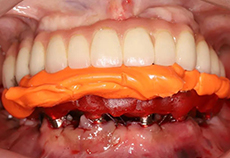

治疗过程:导板引导下下颌外科手术植入6颗种植体

治疗过程:植入6颗种植体

治疗完成